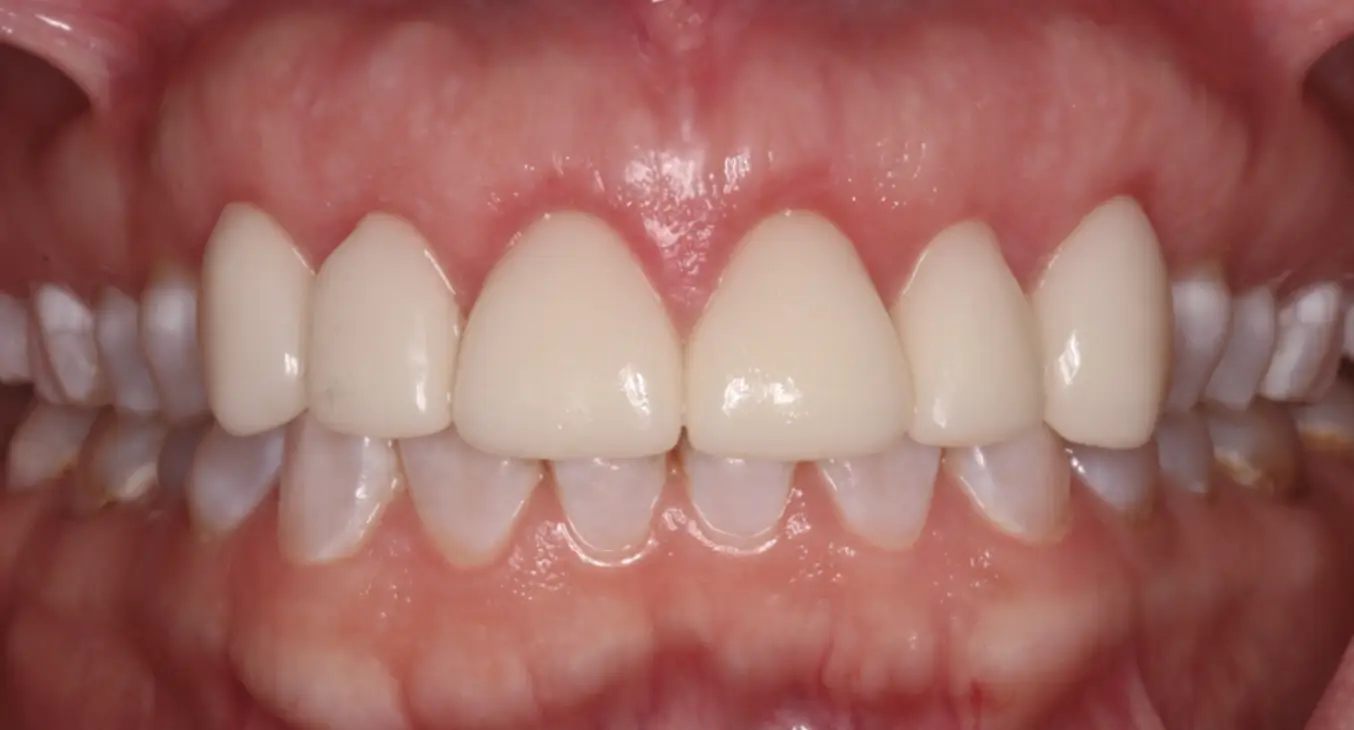

Connective Tissue Graft

before

after